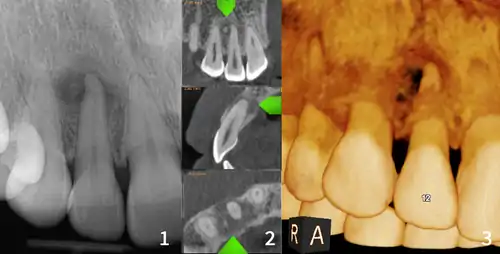

Cemento-osseous dysplasia (COD) is a benign condition of the jaws that may arise from the fibroblasts of the periodontal ligaments. It is most common in African-American females. The three types are periapical cemental dysplasia (common in those of African descent), focal cemento-osseous dysplasia (Caucasians), and florid cemento-osseous dysplasia (African descent). Periapical occurs most commonly in the mandibular anterior teeth while focal appears predominantly in the mandibular posterior teeth and florid in both maxilla and mandible in multiple quadrants.

| Diagnostic method | X-ray, CBCT scan, vitality testing of teeth |

Diagnosis is important so that the treating doctor does not confuse it for another periapical disease such as rarefying osteitis or condensing osteitis. Incorrect diagnosis could lead to unnecessary root canal treatments. It can be diagnosed by radiographic appearance. Confirming the tooth is vital, as is noting the demographic (African American females).